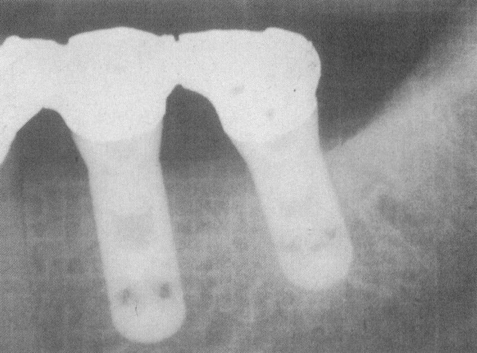

Taurodontia